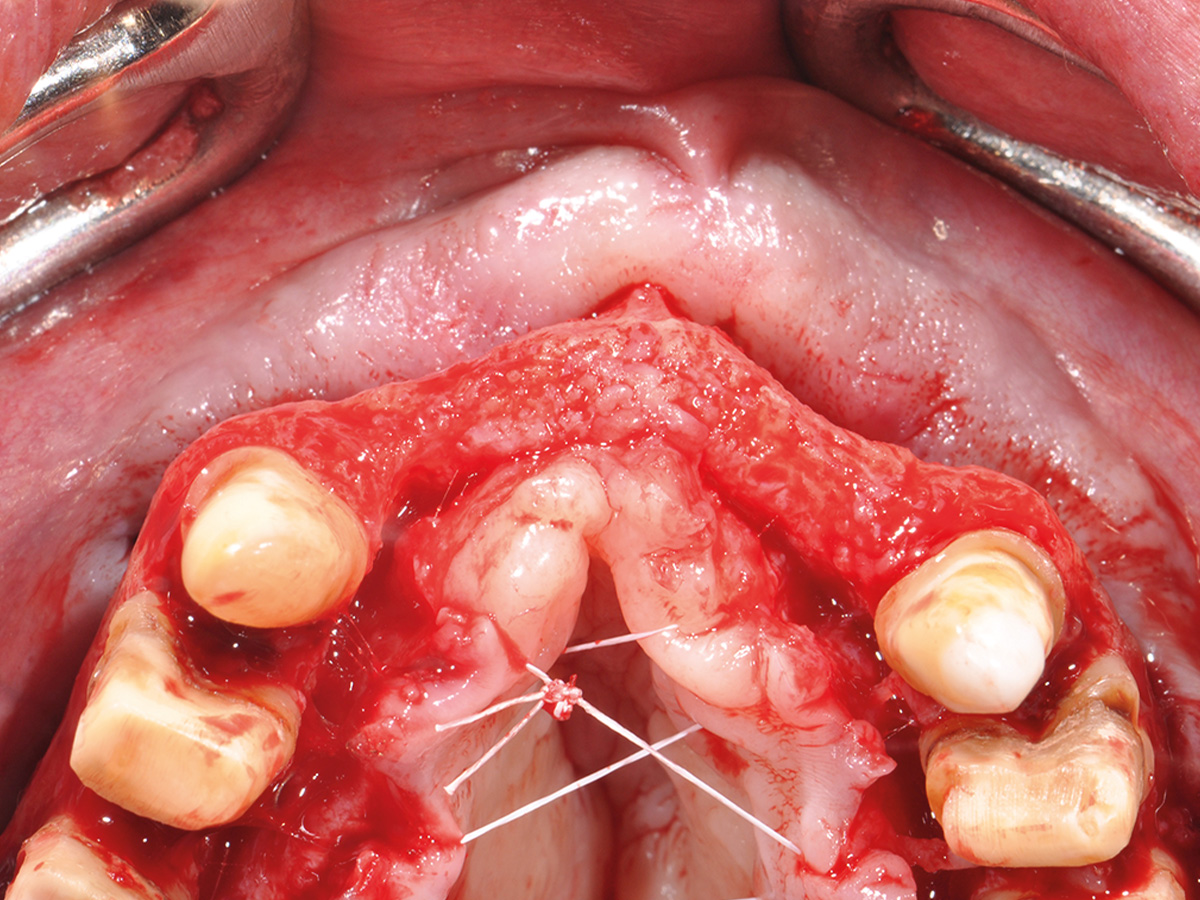

Prinzipien und Konzepte der Knochenaugmentation im Kieferbereich werden logisch aufeinander aufgebaut. Anhand dieser Grundstruktur befähigt der Kurs die Teilnehmer, klinische Situationen fundiert zu analysieren und selbst die logischen chirurgischen Schritte – vom Weichgewebemanagement bis zum Knochenhandling – für die Augmentation abzuleiten.

Im Anschluss werden am Tiermodell alle für eine vorhersehbare Augmentation notwendigen Techniken im Sinne des „Simplify your Augmentation“ eingeübt. Der Weg führt von der einfachen Membrananwendung über die Bone-Lamina- und Double-Layer-Technik bis zur Bone-Shield-Technik. Das Bone Shield ist eine Evolution der klassischen Schalentechnik und erlaubt es, auch komplexe vertikale und kombinierte Augmentationsfälle

im Rahmen der im Kurs vorgestellten Konzeption sicher zu lösen.

Vermittlung des „Simplify your Augmentation“-Konzeptes und Einüben der Bone-Lamina- und Bone-Shield-Techniken am Tiermodell.